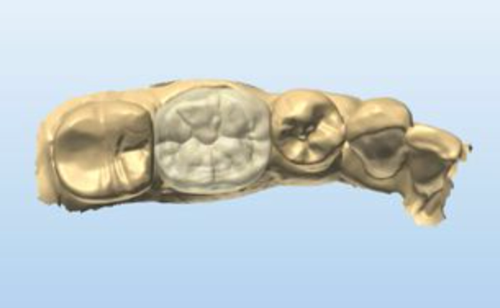

The impression was sent to the laboratory (Peter Kouvaris, New York City) and a lithium disylicate (e.max, Ivoclar Vivadent) crown was prescribed using digital technology. In the lab, Peter scanned the impression and developed the digital information (Fig. 4).

Fig. 4 Fig. 5 Fig. 6

Figure 5 shows a digital image of the teeth in occlusion. Peter designed the crown using digital technology.